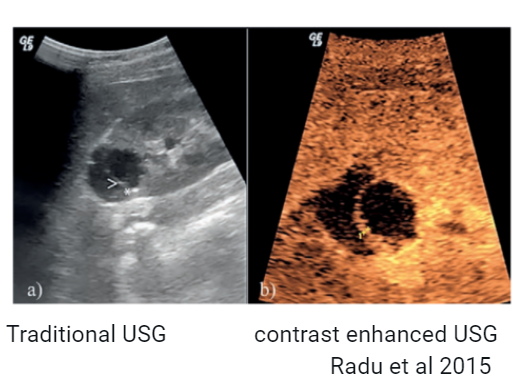

🔹Contrast enhanced USG (fig)- delineates blood blow and microcirculation, differentiates solid vs cystic components, communication with subcapsular space if present etc